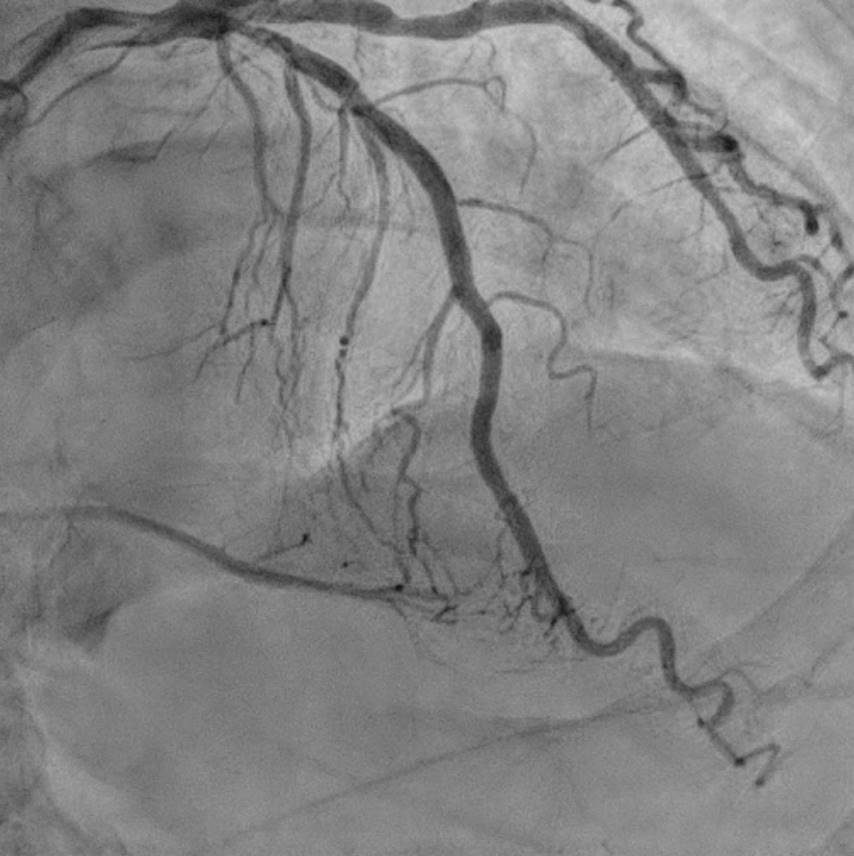

The strategy we plan was antegrade preparation and early retrogradly approach, due to challenging antegrade approach and also distal bifurcation1.XTA+Caravel microcatheter for antegrade preparation, failed advancement in mRCA2.retrograde with suoh03, but could not advance caravel and cosair pro microcatheters through septal channel3.extension catheter use, and balloon dilation for septal channel with low pressure4.caravel could enter dRCA, distal injection5.retrograde wire escalation for calcified CTO: Gaia2, Gaia3, Conquest pro6.kissing wire technique within dRCA7.both side MC could not pass the CTO, despite both side extension catheter use(img: step01)8.intracoronary tip-in, with retrograde wire anchored within AL1(img: step02)9.still failed advancing both side MC10.retrograde balloon dilation, sequentially from distal to middle RCA(img: step03)11.successful antegrade wiring to PL12.lesion preparation and drug-eluting stent placement13.good final angiography results